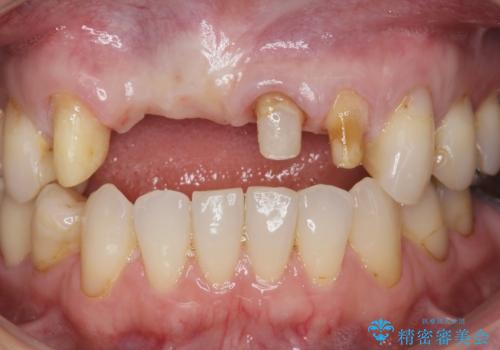

前歯が折れた 前歯部審美セラミックブリッジ治療

- ブリッジの根元が折れ、審美性の改善・治療を求めて来院されました。

保存の難しい歯を抜去しロングブリッジによる補綴を選択しました。